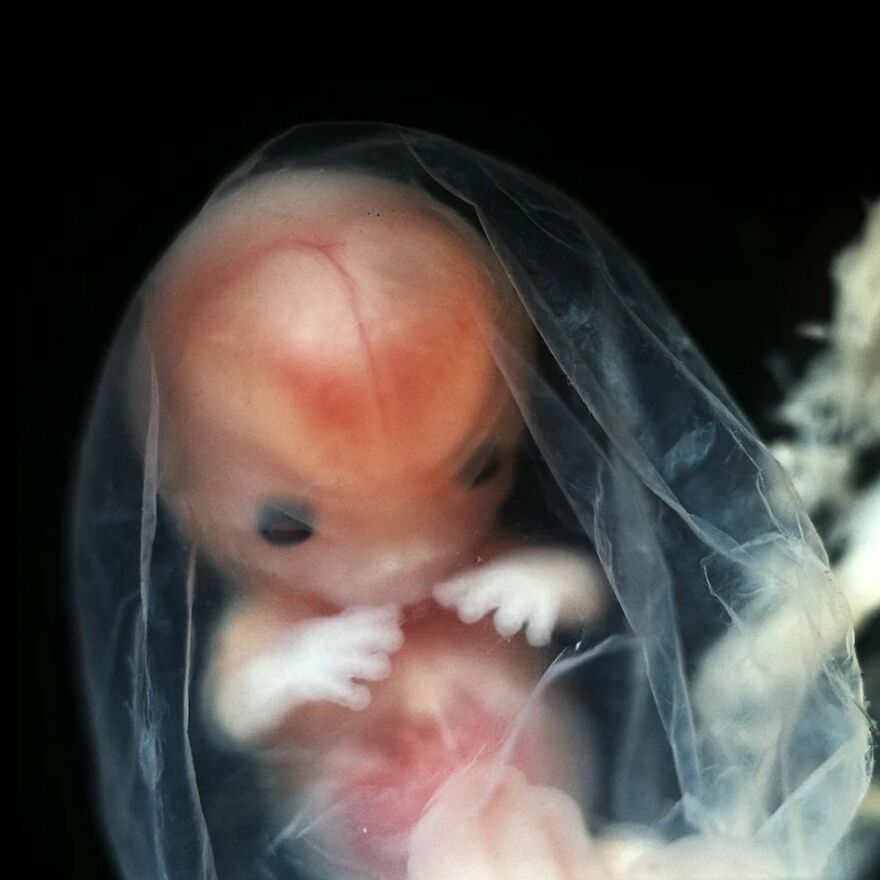

Embryo, 7 weeks, 1990